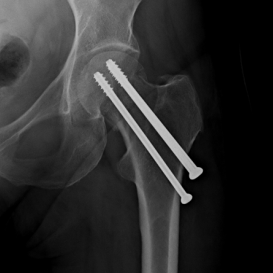

Röntgenbilder